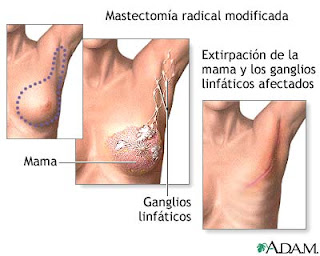

La extirpación es el tratamiento más común de este tipo de lesiones, que puede completarse con la llamada cirugía de Mohs dependiendo de la localización o si la mancha tiene un tamaño considerable.

La escisión simple consiste en la extirpación del tumor y parte del tejido que lo rodea.

Cirugía de Mohs: Se elimina la capa de la piel afectada por el cáncer y más tarde extrae el tejido de alrededor comparando ambos mediante pruebas en el microscopio. * Criocirugía: Mediante nitrógeno líquido se congelan y destruyen las células cancerosas.